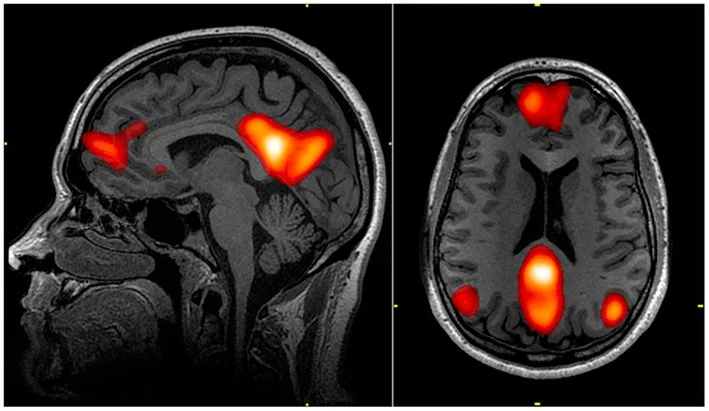

When someone enters a non-ordinary state (aka, gets high) with the intention to heal, a part of the brain known as the Default Mode Network (DMN) lights up on brain scans. This area is responsible for our sense of self—the "me, myself, and I" network. It answers the question: Who am I?

Magic mushrooms (psilocybin) activate the DMN—the part responsible for choosing the words that follow your "I AM" statements. Think of psychedelics as a truth serum. They allow you to see the reality of who you are by exposing false "I AM" statements.